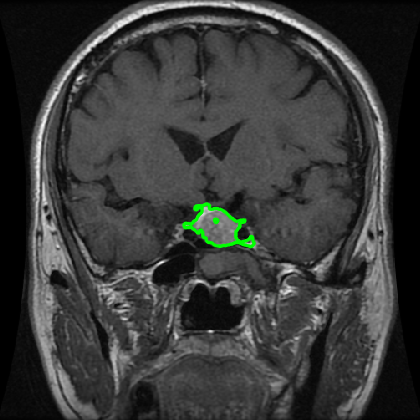

From the above discussions, we have discovered the significant potential of applying Retinex theory to image segmentation and explored its fundamental differences from traditional models. Traditional image segmentation models typically focus on the impact of intensity information on the segmentation results. Therefore, when faced with complex segmentation scenarios, the segmentation results are often affected by lighting, artifacts, and unclear boundaries in the image. As shown in Fig. 1, we present the results of the classical local model LIF [ZHANG20101199] for segmenting brain tumor images along with surrounding tissue edema. The irregular ring-like enhancement caused by the edematous tissue leads to irregular boundaries and low contrast in the images. Consequently, the LIF model can only identify the central necrotic and liquefied regions of the tumor, failing to detect the boundaries and becoming trapped in local minima. In this paper, we draw inspiration from the Retinex theory, which is widely applied in the field of image enhancement. According to Retinex theory, the reflectance component characterizes the intrinsic structural properties of the observed image and preserves texture information independent of illumination variations. By integrating this reflectance component into the level set framework, our model achieves robust segmentation of medical images even under severe intensity inhomogeneity. In addition, a linearized Structural-Prior is proposed to restore intensity consistency and capture local geometric features, thereby improving boundary localization in complex or blurred regions. Furthermore, a relaxed binary level set representation is employed to enhance robustness against noise and to enable accurate tracking of complex contours. Based on these innovations, we propose a novel variational reflectance-based level set model (RefLSM) that simultaneously corrects bias fields and performs segmentation. Experimental results demonstrate that RefLSM significantly outperforms conventional level set methods in both segmentation accuracy and robustness. We present the results of our model segmenting the two brain tumor images mentioned above in Fig. 2.

To address the challenge of segmenting images with severe intensity inhomogeneity, we propose a linearized structural prior that directly operates on the reflectance component . Reflectance-based structural information is more robust to illumination variations and bias field distortions, helping preserve weak edges and subtle anatomical boundaries. As shown in Fig. 2, our method can accurately delineate tumor boundaries and surrounding edema even under severe inhomogeneity, where traditional intensity-based models often fail. The proposed prior aligns smoothed reflectance gradients with data-driven directions, enhancing inter-region contrast, preserving weak edges, and stabilizing the evolution of . Formally, we define the linear structure operator as the gradient field of the smoothed reflectance: